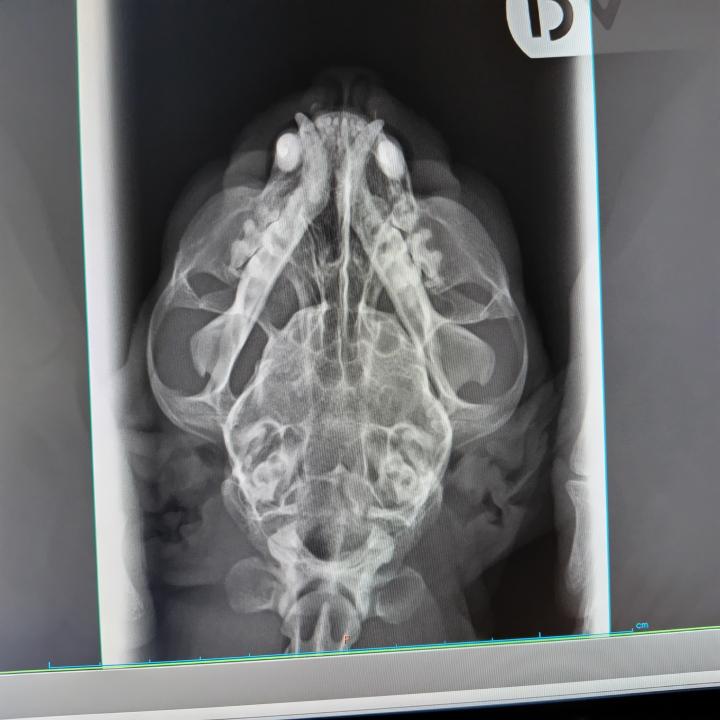

二週間に一度の検診時にレントゲン撮ってきました

上から

変な影もなく、見た目問題ないので

次に血が混じるなら、本格的な検査と

止血剤を考える事になりました